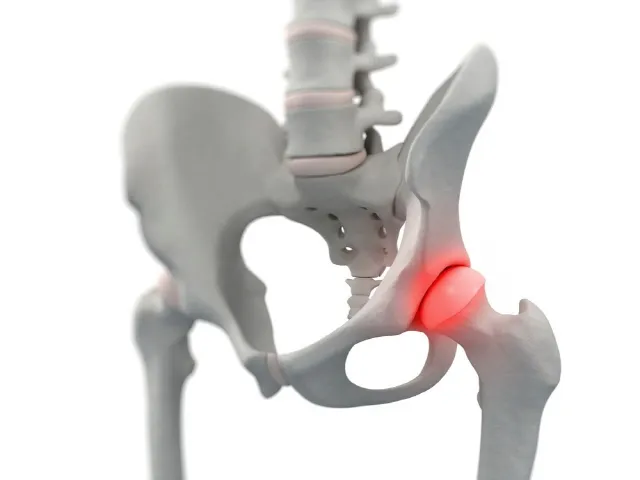

골반 부위에 통증이 나타나면 흔히 "파"로 알려진 "절뚝거림"으로 이어지는 경우가 많습니다. 고관절 통증은 크게 세 가지 방향으로 나뉩니다: ▲서혜부(사타구니) ▲측면 ▲후면으로, 각각의 방향에 따라 의심되는 질환이 달라집니다. 그중 가장 많이 보고되는 증상은 사타구니 통증입니다.

고관절 발달 이형성증이나 대퇴골두 충돌 증후군이 있을 경우, 대퇴골두의 무혈성 괴사가 말초 골절로 확장되면 사타구니 부위에 통증이 발생하는 것이 보통입니다. 고관절 외측의 통증은 주변 연부 조직의 손상 또는 염증으로 인한 대전자 통증 증후군(GTPS)과 관련이 있으며, 고관절 후방 통증은 주변 근육의 긴장이나 비대로 인해 이상근 증후군이 좌골 신경을 압박하는 상황에서 발생할 수 있습니다.